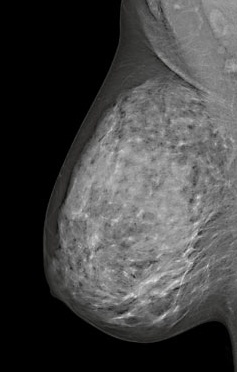

FDA Approves Stand-alone 3D Screening With Siemens Tomosynthesis Platform

Breast Density Notification Laws - Quick Tips to Educate Providers and Patients

Breast Density Notification Laws Increase in Legislation

Cassling is Proud to Partner with Siemens Healthcare for Women's Health, Now Offering 3D Mammography

FDA Approves Breast Tomosynthesis Option for Siemens Mammography Platform